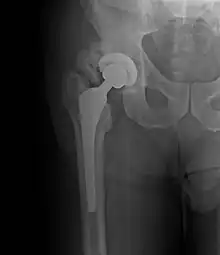

Ossification hétérotopique de la hanche